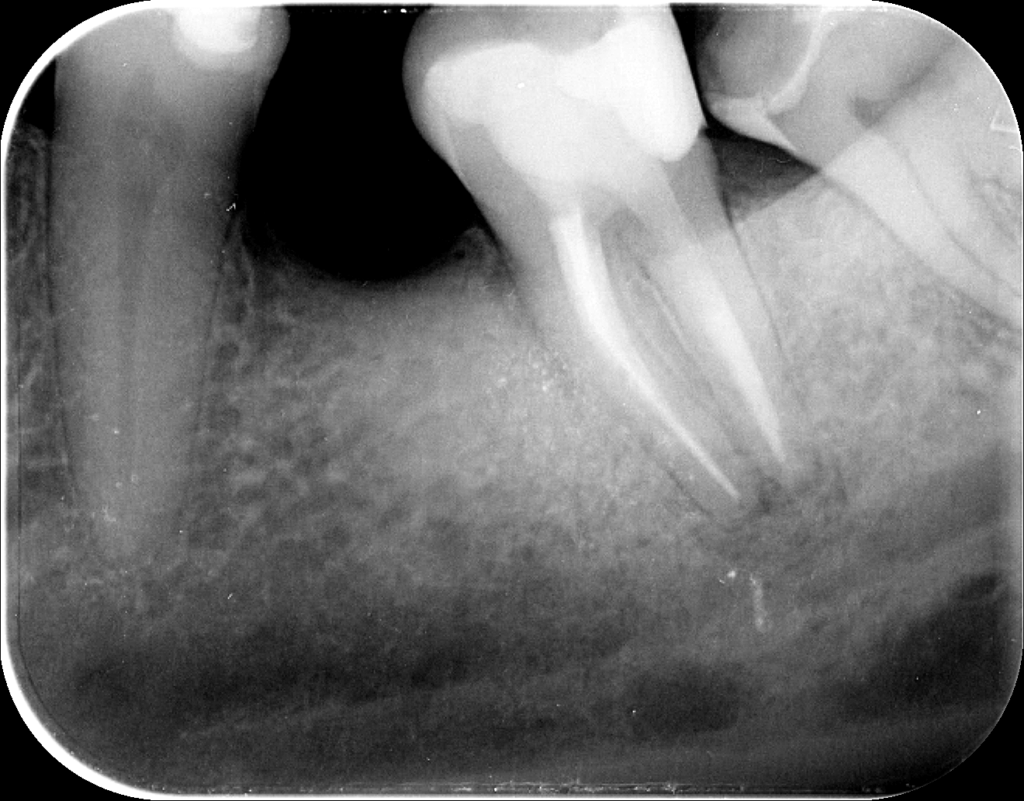

Első alkalommal eltávolítottuk a régi gyökértömést, megkerestük a csatornák végét, illetve a hátulsó gyökérben találtunk még egy, addig fel nem fedezett csatornarészletet. Ezt követően különböző vegyszerekkel kitisztítottuk a fogat, és gyógyszert tettünk a gyökércsatornákba. Második alkalommal készítettük el az új gyökértömést. Nagyjából egy hét telt el a két ülés között, és a páciens panaszai máris nagymértékben csökkentek. Pici ráharapási érzékenység volt tapasztalható, de ezt normálisnak tekintjük a kezelések között, egyes esetekben a gyökértömés befejezése után is, legalábbis egy kis ideig. A gyökértömés után üvegszálas csapos megerősítést helyeztünk a fogba.

Fog megmentése mikroszkópos kezeléssel gyökértömés

3

A gyökértömést követően a pácienst fél év múlva rendeltük vissza egy kontroll röntgenfelvételre. Saját elmondása szerint a gyökértömést követő pár napban még érzékeny volt a foga, azóta azonban teljesen panaszmentes. Mint az a felvételen is jól látható, a csontban lévő kezdeti fekete elváltozás mára már teljesen eltűnt, helyét az egészséges, ép csontszövet vette át. Készülhet a korona a fogra!

Fog megmentése mikroszkópos kezeléssel eredmény